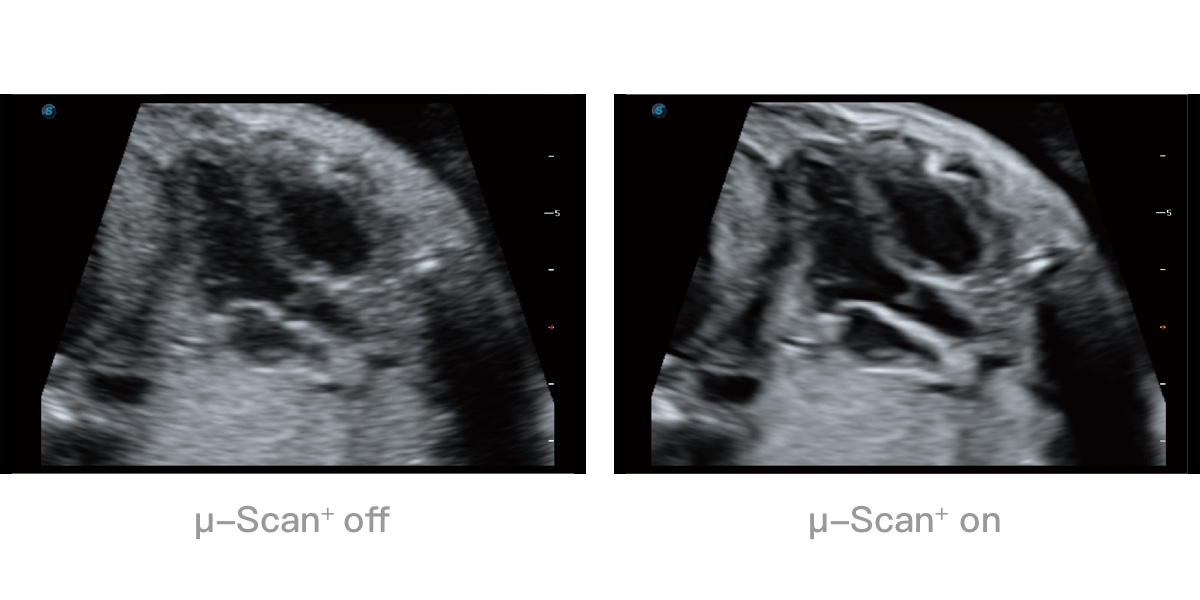

• μ-Scan微米成像技术

微米成像技术提升了对组织斑点噪声信号的抑制能力,并进一步强化边界信息,从而获得清晰图像。